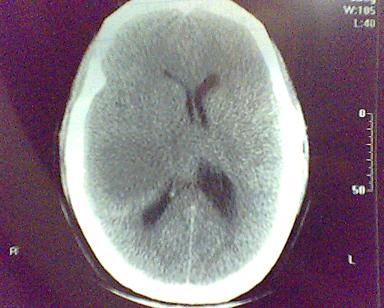

男 31岁 短暂性四肢抽搐 呼叫不应  头胀痛4个多月 无发热 4年前遭棒击头部,当时未到医院检查。余无特殊。病人特穷,未作增强。

这是一个边缘清晰的等密度的囊性占位.密度比较均匀,周围无水肿,我顷向于脑脓肿的可能性大.

右侧乳突蜂房消失,右侧颞叶区囊性占位,水肿不明显,考虑表皮样囊肿或耳源性脑脓肿,+c!。